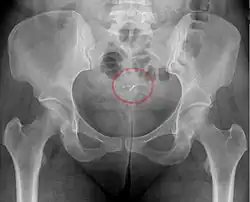

- Perforación: muy rara vez, el diu se puede empujar a través de la pared del útero durante la inserción. El riesgo de perforación está determinado principalmente por la habilidad del médico que realiza la inserción. Para médicos experimentados, el riesgo de perforación es de 1 por 1000 inserciones o menos. Con las inserciones posparto, la perforación del útero es más probable que ocurra cuando la involución uterina es incompleta; La involución por lo general se completa entre 4 y 6 semanas después del parto. Se aplican consideraciones especiales a las mujeres que planean amamantar. Si se produce una perforación, puede dañar los órganos internos y, en algunos casos, se necesita cirugía para extraer el diu.

- Una "espiral perdida" ocurre cuando el hilo no puede ser sentido por una mujer en la revisión de rutina y no se ve en el examen con espéculo. Se pueden usar varios dispositivos colectores de hilo o pinzas simples para tratar de agarrar el dispositivo a través del cuello uterino. En los casos poco frecuentes en que esto no sea posible, se puede realizar una ecografía para verificar la posición de la espiral y excluir su perforación a través de la cavidad abdominal o su expulsión previa no reconocida.